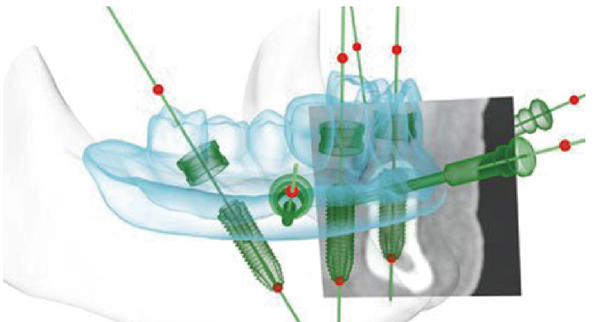

苏州美奥口腔王汉禹院长介绍,计算机三维专业种植导板配合All-on-4即刻负重种植手术,在缩短手术时间,专业定位种植位置,提升种牙安全性上展现了智能科技的专业优势。

三维专业种植导板在多颗,半/全口种植中,能在种牙前对牙骨的高度、宽度、深度进行测量并动画模拟真实手术。也就是说在真实手术前,医生就在计算机生成的三维影像上进行了一次种植手术预演,预先标注专业的种植位置,最终制作成一个种植导板。

患者在手术时,将导板佩戴在口腔内,医生可以根据导板上的标注位置确定种植位置,而不是通过传统的人眼目测,大大提高了种植的精确性和降低手术风险,手术时间大幅度缩短,降低了患者的痛苦,条件允许可实现微小切口、不翻瓣、无缝合的手术治疗。

▲三维导板确定种植牙位置